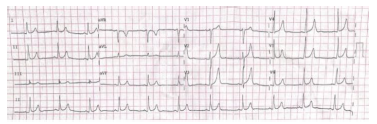

Gasometria arterial: pH 7,20, pCO2 25 mmHg,

HCO3 11 mEq/L, pO2 60 mmHg. Glicemia

capilar 200 mg/dL. ECG conforme imagem: